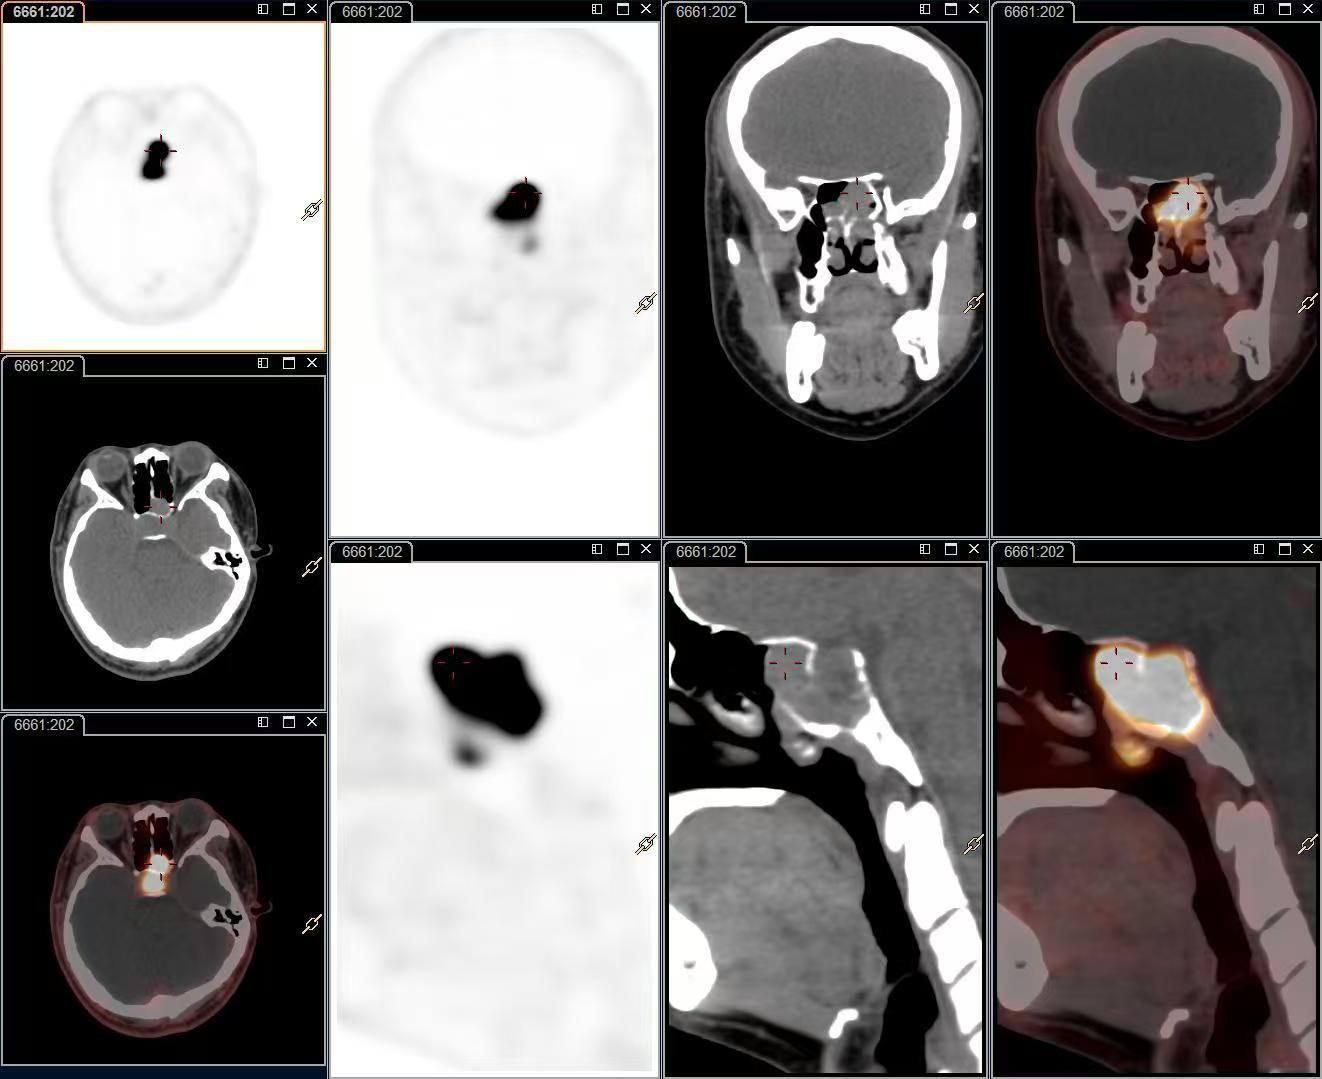

近日,核医学科成功开展了我院首例奥曲肽PET/CT神经内分泌肿瘤显像检查,为神经内分泌肿瘤的早期诊断、精准分期、疗效评估提供了全新的解决方案,标志着我院在肿瘤分子影像诊疗领域的新征程。

本次显像病例是一位24岁的年轻男性患者,因左侧鼻塞活检提示神经内分泌肿瘤(NET,G2),免疫组化提示SSTR2(3+),患者行治疗前评估。核医学科团队在充分告知并取得知情同意后,为该患者进行18F-奥曲肽PET/CT显像。结果显示,18F-奥曲肽 PET/CT能明显显示病灶范围,充分体现了18F-奥曲肽PET/CT在神经内分泌肿瘤诊疗中的优势。